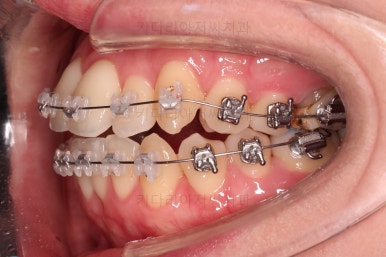

초진 시, 입안의 모습입니다.

좌측 송곳니가 덧니처럼 튀어나가 있고, 송곳니 옆의 작은 억므니가 안으로 쏙 들어가서 덧니 느낌이 더 강조되어 보이네요.

위아래 앞니가 긴밀하게 겹침이 없는 약간의 개방교합(오픈바이트, Openbite) 경향이 보입니다.

웃거나 말할 때 드러나는 치열이 삐뚤어서 심미적으로 좋지 못하고요.